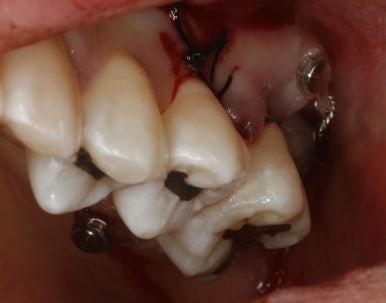

일도 힘들었을텐데 꼬박 꼬박 진료도 잘 와줘서 사랑니가 원래 제 자리였던것처럼 위치하고 있다.

비용도 수고로움도 임플란트만큼이지만 치주인대를 갖고있는 나의 치아로 대체할 수 있음은 충분히 투자가치가 있다는 개인적인 의견이다...